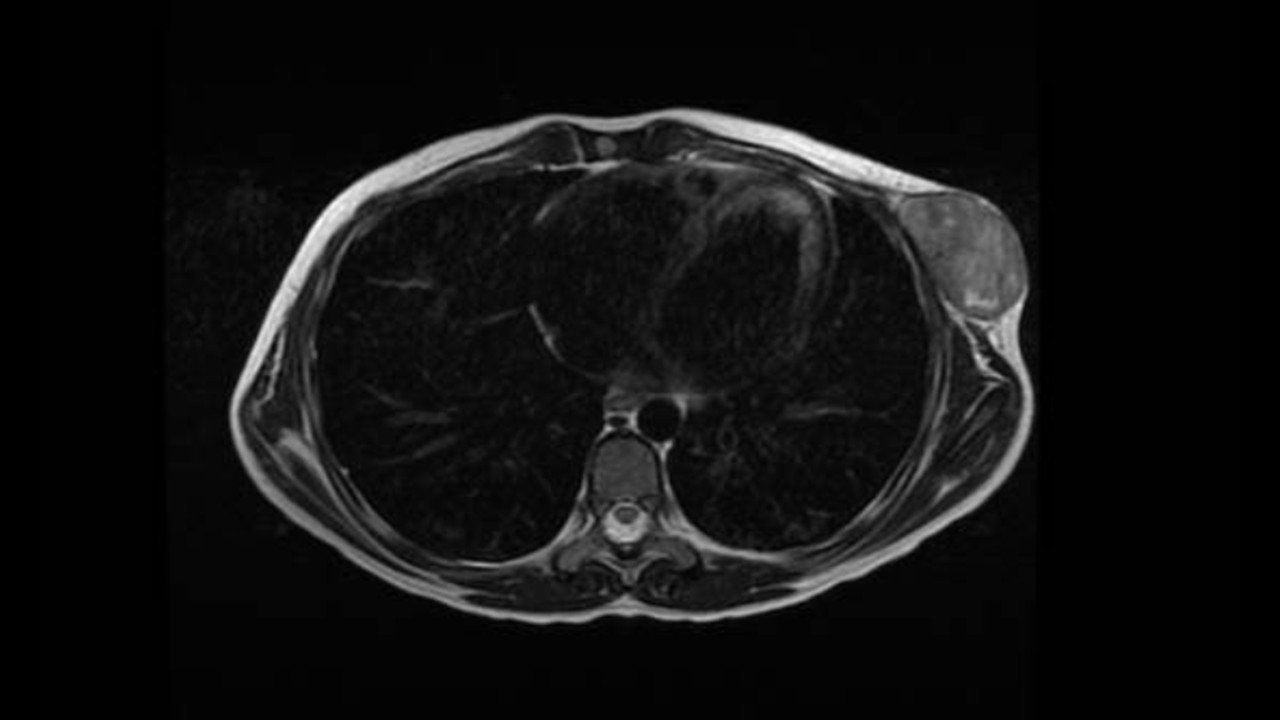

TAC: Lesión a nivel de la región axilar anterior a la altura de los arcos costales 5º y 6º izquierdos; es redondeada, de contornos bien definidos, de aspecto lobulado, hiperintensa en T1 y cuyas dimensiones son de 31 x 50 x 54 mm.